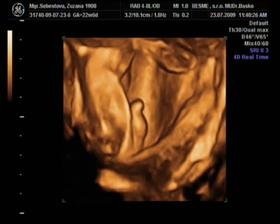

nas druhý pokladík, Radimko jr., (inak batôžtek, keď neposlucha - batoh) sa nam prihlasil na tento svet 17. 11. 2009 (v utorok) o 10.05 h., s mierami 4040g a 54 cm.